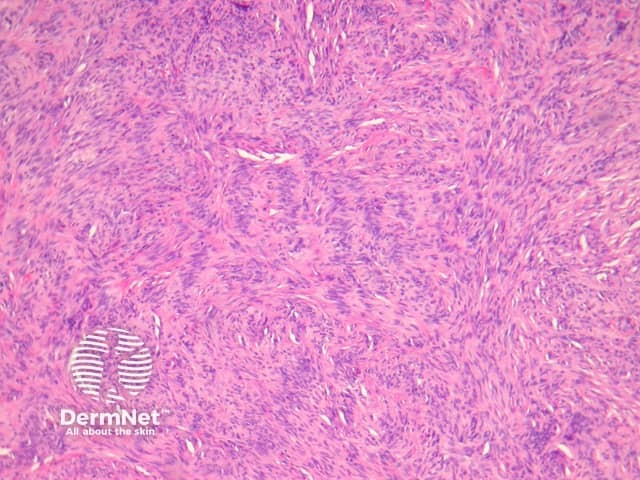

Compared with usual dermatofibroma, cellular dermatofibroma has an increased chance of recurrence following excision and metastasis is reported. Histologically, there is increased cellularity with a swirling, storiform pattern (figures 3,4). Peripheral entrapment of collagen is less prominent in this variant. There may be increased mitoses and extension to the subcutaneous fat, which are associated with more aggressive behaviour. Approximately 10% of cases show central necrosis.

Cellular dermatofibroma may resemble dermatofibrosarcoma protuberans, which can be differentiated by its larger size, increased mitoses and marked involvement of the subcutis. CD34 is positive in dermatofibrosarcoma protuberans and is usually negative in dermatofibroma, although the cellular variant may have focal positivity, especially at the periphery of the lesion. A study of clonal karyotype abnormalities in dermatofibroma found cellular dermatofibromas were more likely to have karyotype abnormalities than common dermatofibromas.

Figure 3

Figure 4